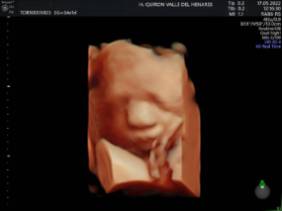

El Hospital Quirónsalud Valle del Henares ofrece la posibilidad de realizar ecografías gestacionales 5D. Este tipo de exploración permite obtener una imagen muy realista del bebé y se puede realizar en cualquier etapa de la gestación -aunque lo recomendado es realizarla entre las semanas 28 y 32 de gestación, ya que técnicamente es el mejor momento y es mucho más probable obtener imágenes de buena calidad-.

"Realizar esta ecografía con nuestro equipo de diagnóstico prenatal tiene un valor añadido -señala la Dra. Rocío Vellido Cotelo, Jefa Asociada de Ginecología y Obstetricia del Hospital Quirónsalud Valle del Henares, dado que quien realiza la prueba es un especialista en la materia, siempre se completa la exploración con un examen morfológico y de perfil biofísico fetal, que permita valorar el estado de bienestar del bebé más allá de la captura de videos y fotografías".